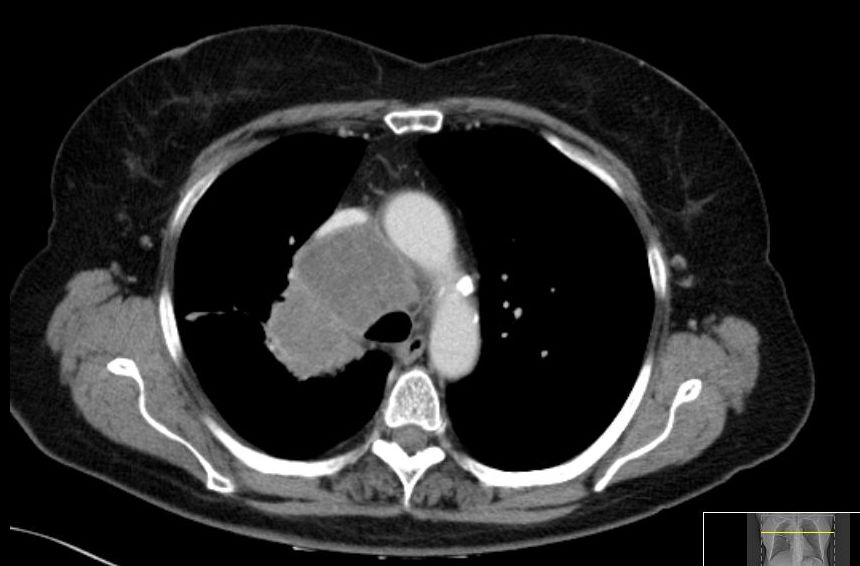

Zentrales kleinzelliges Karzinom rechts. Typisch für Kleinzeller ist die fließende Ausbreitung im Mediastinum.![]() |